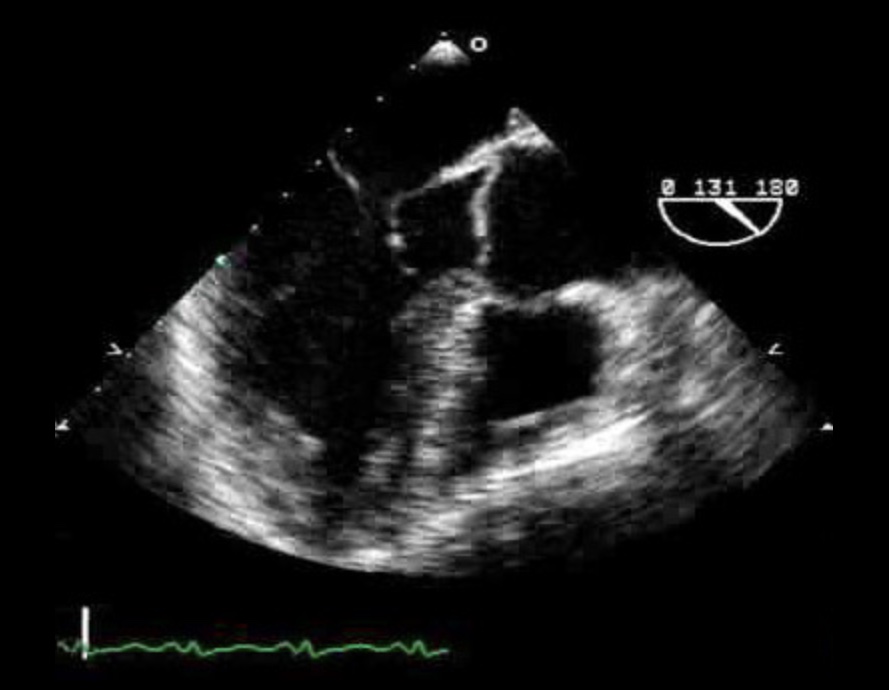

ID this view and the structures.

ME2C